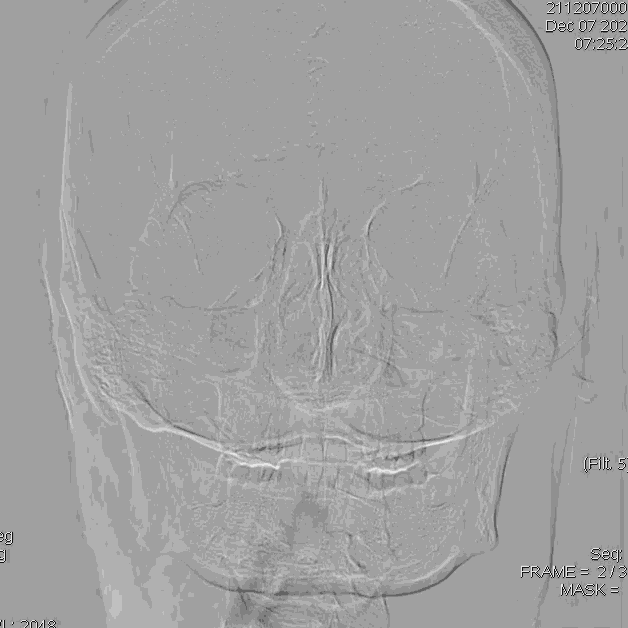

术前造影:提示左侧颈内动脉起始段闭塞,左侧大脑后动脉后交通开放,代偿左侧大脑中动脉部分供血区。